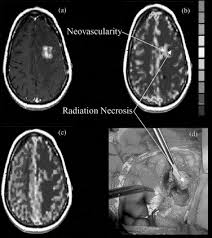

Cureus Giant Cerebral Tuberculoma Masquerading As Malignant Brain Tumor A Report Of Two Cases

Cureus Giant Cerebral Tuberculoma Masquerading As Malignant Brain Tumor A Report Of Two Cases from assets.cureus.com